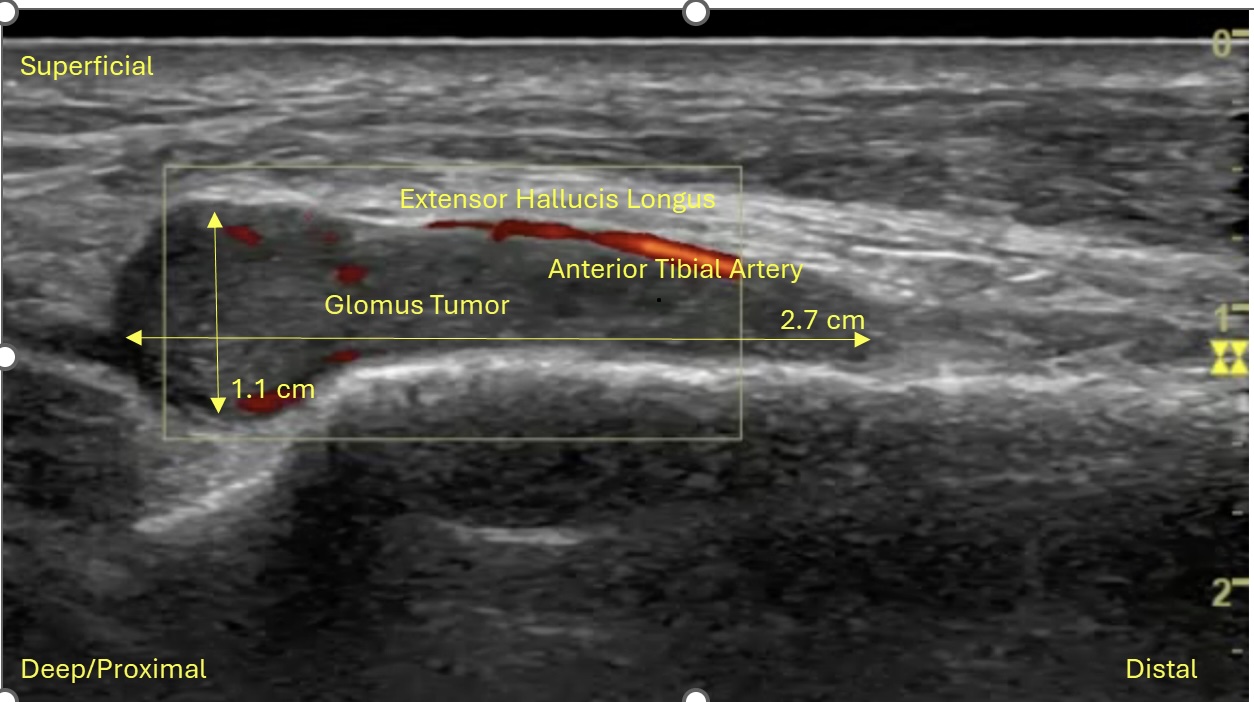

Image Interpretation: LAX view, ill-defined mass abutting the anterior tibial artery between the tibialis anterior and extensor hallucis longus tendons. 2.7 x 0.8 x 1.1 cm. Notable blood flow proximally and within mass observed with Doppler.

Teaching Pearl: Glomus tumors typically present in the upper extremities (particularly the hand/fingers) and as such can often be difficult to diagnose in other parts of the body. Patients with glomus tumors often have pinpoint tenderness, paroxysmal pain, and cold sensitivity. Clinical diagnosis can be tricky as those three characteristics are often isolated and less frequently occur together. US/MRI are the diagnostic imaging modalities of choice. US with doppler can be helpful in diagnosis as they can be mistaken for other benign masses and can help assist in the evaluation of an arterial supply feeding the tumor. A case series from the Hospital for Special Surgery (HSS) over the course of 18 years excised 11 glomus tumors from the foot, with the majority of them located in the distal hallux.1 The glomus tumor from this case matches descriptions of other extradigital glomus tumors, including a "vascular stack", however it is larger in size compared to the mean size (1 cm) from a study analyzing non-subungal glomus tumors.2 Typical glomus tumors are visualized as small, well-circumscribed, hypoechoic nodule with prominent arterial flow (vascular stalk).